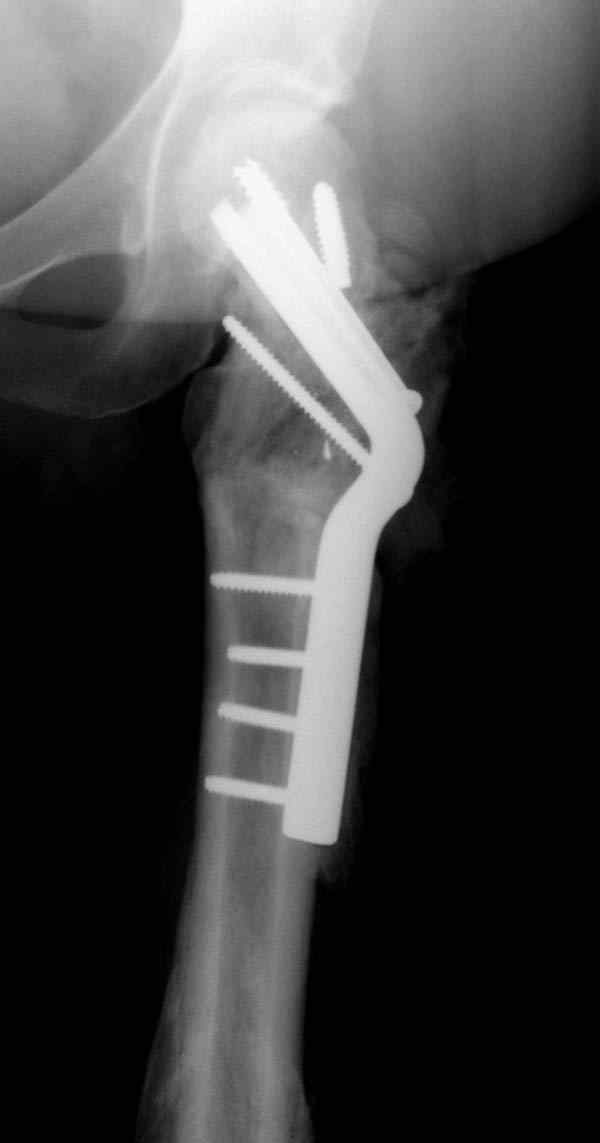

Несмотря на пессимистические прогнозы, у молодых

коррегирующая вальгусная остеотомия является более

приемлемым.

Представленные случаи доказательства тому, что еще

имеется резервы на восстановление даже у 5-6 месячных ложных суставов шейки.